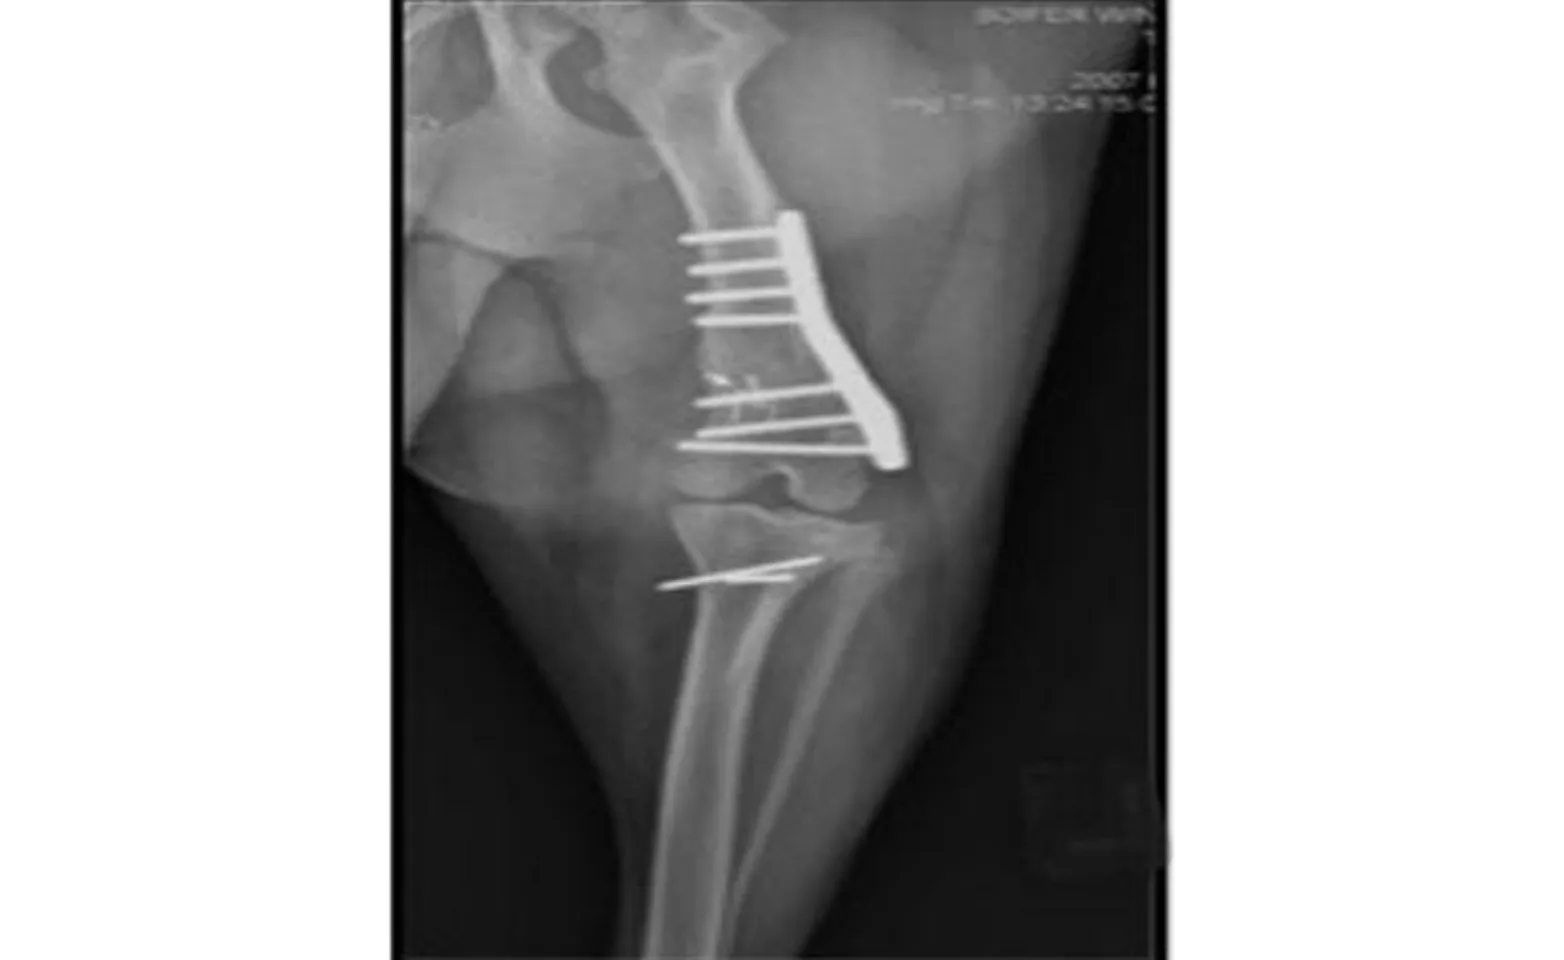

In large breed dogs an angular deformity of the femur, termed femoral varus, is commonly identified. If femoral varus is significant then correction is often required in addition the procedures listed above. Correction of femoral varus correction is performed by removing a wedge portion of bone from the femur, known as a distal femoral osteotomy, and then stabilized of the bone with a plate – as is common with fractured bones.

This shows a post-operative radiograph of a dog that had a femoral varus correction performed. A tibial tuberosity transposition was also performed as noted by the pins located beneath the stifle joint. (Courtesy Dr. Sharon Kerwin, Texas A&M University)